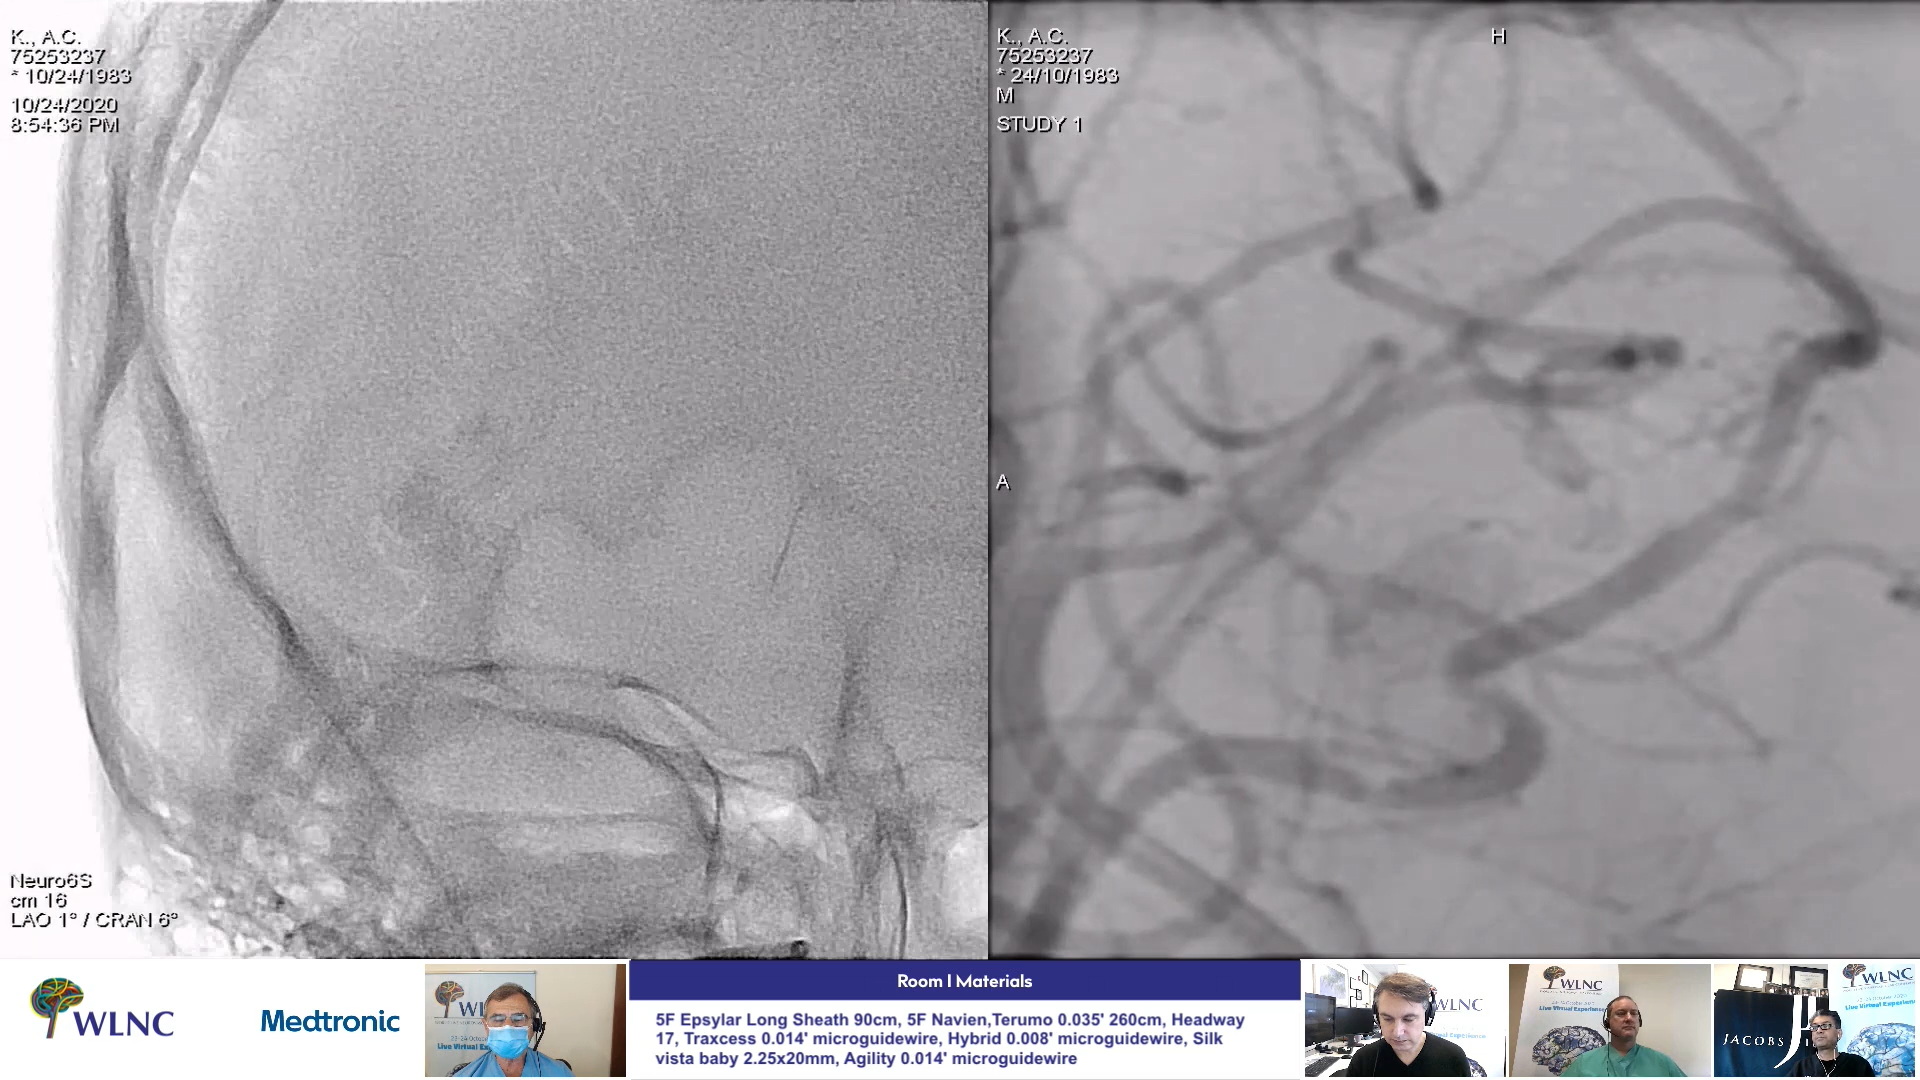

WLNC LIVE & WARM-UP CASES

WLNC 2020 - SECOND DAY

WLNC 2020